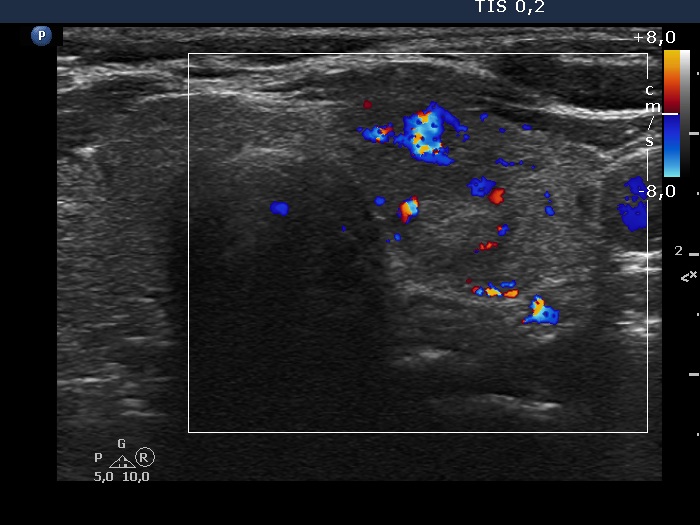

Left lobe, another transverse view, color Doppler mode.